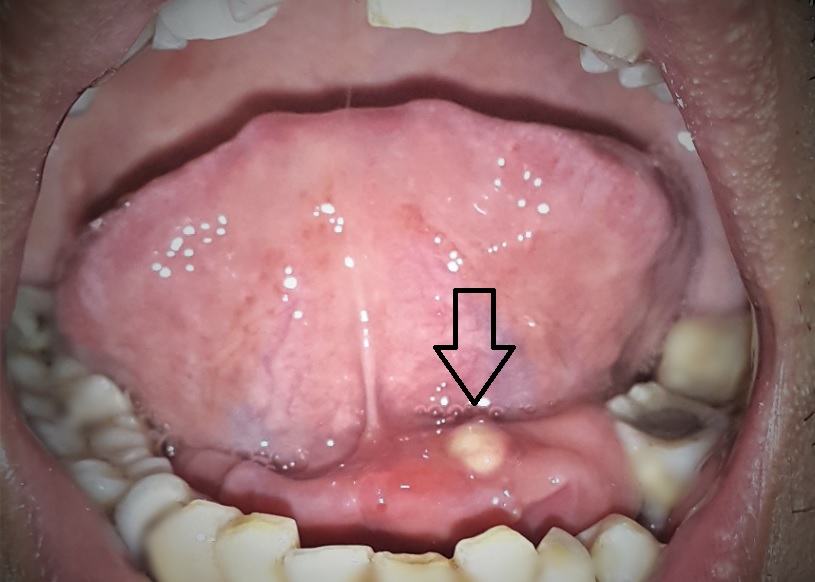

Inilah Penyebab Benjolan di Lidah Perlu Anda Waspadai Mengenal Penyakit Lidah dan Cara Mengatasinya - Alodokter Muncul Benjolan di Lidah Rafathar, Respon Raffi Ahmad Ini Bikin Nagita Kesal : Kamu Santai Banget - Tribunnews.com Mobile Ada Benjolan di Bawah Lidah Rafathar, Kenali Gejala Penyakit Mucocele! 5 Tanda Anda Kena Kanker Lidah - Lifestyle Bisnis.com Alami Sembelit Selama 3 Bulan, Lidah dan Bibir Sakit Hingga Usus Digerogoti Tumor - Semua Halaman - Grid Health Lidah Rafathar Ada Benjolan Aneh, Nagita Slavina Panik & Kesal dengan Raffi Ahmad yang Justru Santai - Tribunnewsmaker.com Waspadai Ciri-Ciri Kanker Lidah yang Sering Diabaikan - Health Liputan6.com Waspada Ruam Kulit dan Benjolan Kecil Pada Lidah, Peneliti Ungkap Bisa Jadi Gejala Covid-19 - Zona Jakarta Benjolan di Bawah Lidah Dapat Disebabkan Penyakit Ini | HonestDocs 5 Ciri-Ciri Kanker Lidah yang Paling Mudah Dikenali Waspada Ya, 7 Gejala Kanker Lidah Ini Mirip dengan Sariawan | IDN Times Jabar Terlibat Cek-cok dengan Raffi Ahmad Bahas Benjolan di Lidah Rafathar, Nagita Slavina : Kamu Tuh Santai Banget - Semua Halaman - Hype Penyakit Kanker Lidah yang Tak Boleh Diremehkan, Kenali Gejala dan Penyebabnya - Hot Liputan6.com Menebak Kondisi Kesehatan Seseorang Lewat Lidah - Foto 7 Untuk Para Ibu, Waspada Jika Ada Benjolan di Mulut Anak - Tribun Jambi Ada Benjolan di Lidah? Hati-hati, Bisa Jadi Gejala COVID-19 Gejala Kanker Lidah Apa Saja yang Perlu Anda Ketahui? Gejala Baru Virus Corona, Benjolan Kecil di Lidah Bisa Jadi Covid-19 Halaman all - Kompas.com Risiko, Gejala, Pemeriksaan dan Pengobatan Kanker Lidah - RS Kanker FUDA Selain Covid-19, Benjolan di Lidah Bisa Juga Tanda Kekurangan Vitamin B12 Mucocele, Benjolan Mirip Kista Di Mulut | Waspada Ya, 7 Gejala Kanker Lidah Ini Mirip dengan Sariawan | IDN Times Jabar Obat Benjolan di Lidah - Propolis SM di Kota Surabaya | Lazada Indonesia Cari Tahu Penyebab Sialolithiasis Mengapa Muncul Tonjolan di Lidah Saya ? [Bagian Kedua] | Global Estetik Waspada, Benjolan di Lidah Bisa Jadi Pertanda Kanker 6 Gejala Kanker Lidah Yang Tak Bisa Dianggap Sepele, Bisa Juga Terasa di Telinga - Halaman all - Tribun Bali Cek Lidah Kamu Sekarang, Tanda Ini Bisa Jadi Gejala Penyakit Berbahaya Hati-hati, Benjolan di Lidah Ternyata Gejala Covid-19, Kok Bisa ya? - Mantra Sukabumi Obat Benjolan di Lidah - Obat Benjolan di Bawah Lidah - Obat Benjolan Lidah - Propolis SM | Lazada Indonesia Kanker Lidah dan Mulut, Seperti Apa Wujud Gejala Awalnya? Hachijo Herbal - Testimoni Benjolan di bawah Lidah… | Facebook Raffi Ahmad dan Nagita Kaget Ada Benjolan di Bawah Lidah Rafathar | Popmama.com Kanker Lidah | Gejala, Diagnosis, Pengobatan Cara Menghilangkan Benjolan Di Lidah | caramenghilangkanbenjolandilidah Ada Benjolan Kecil di Lidah? Awas Bisa jadi Gejala COVID-19 Penyakit Kanker Lidah - Gejala, Penyebab, Pengobatan - Klikdokter.com Coba Gulung Lidah Ke Atas, Jika Ada Urat Hitam Di Bawah Lidah, Anda Dalam Bahaya, - Sriwijaya Post Ada Benjolan Aneh di Lidah Rafathar, Nagita Slavina Panik, Begini Respon Raffi Ahmad | Tribun Style | LINE TODAY Obat Benjolan di Lidah, Telinga di Bawah Kulit di Payudara Wanita di Ketiak di Belakang Propolis SM | Shopee Indonesia konsul pasien dengan benjolan di lidah 1 minggu, keganasan kah ? - Diskusi Dokter Ini 4 Penyebab Lidah Bengkak dan Timbul Benjolan - Zact Toothpaste Cara Mengobati Benjolan Di Lidah Secara Alami Dan Ampuh - DetikForum 3 Cara untuk Menghilangkan Benjolan di Lidah - wikiHow Ini Dia 5 Penyebab Penyakit Lidah yang Bisa Anda Derita - Womantalk Muncul Benjolan di Lidah Jadi Gejala Virus Corona, Benarkah Begitu? - RCTI+ INI GEJALA KANKER LIDAH | Beritahu.info Hubungan Intim tidak Sehat Bisa Picu Kanker Lidah? Dokter Spanyol Sebut Benjolan di Lidah Bisa Jadi Tanda Infeksi Covid-19 Modern Cancer Hospital Guangzhou, China Jangan Anggap Remeh, Deteksi Penyakit dalam Tubuh Lewat Warna Lidah | Indozone.id Waspada Ya, 7 Gejala Kanker Lidah Ini Mirip dengan Sariawan | IDN Times Jabar 3 Cara untuk Menghilangkan Benjolan di Lidah - wikiHow Jangan Abaikan, Benjolan di Lidah Bisa Jadi Gejala Virus Corona Covid-19 - HiMedik.com Lidah Bengkak dan Timbul Benjolan, Perhatikan 4 Ini Sebabnya - Beauty Fimela.com Kenali Kanker Lidah Gejala Awal Mirip Sariawan – Kaba12.com Ciri Ciri Gejala Kanker Lidah Stadium Awal Mulai Sariawan hingga Benjolan - YouTube 5 Penyebab Lidah Sakit yang Perlu Diperiksa Dokter Ciri-ciri Kanker Lidah Stadium Awal Halaman all - Kompas.com Benjolan di Bawah Lidah Dapat Disebabkan Penyakit Ini - Alodokter Apa yang Menyebabkan Benjolan di Lidah? | Kafe Kepo | Benjolan tumor pada lidah - YouTube Mengenal Penyakit Geographic Tongue yang Menyerang Lidah - Tirto.ID Bongkar Gejala Baru Covid-19, Peneliti Spanyol Kaget, Ternyata Benjolan di Lidah Perlu Diwaspadai - Pikiran Rakyat Pangandaran Gigi Panik Ada Benjolan di Bawah Lidah Rafathar – FAJAR Obat Benjolan Di Lidah Untuk Anak, Balita Dan Bayi | Obat Penyakit Uci Uci Kanker Lidah, Ketahui 5 Ciri - cirinya - Cantik Tempo.co Kanker Lidah Bisa Sebabkan Kematian. Apa Pemicunya? - Info Sehat Klikdokter.com Jual Obat Benjolan Gusi - Benjolan Mulut - Benjolan Lidah - QnC Jelly Gamat - Kota Tangerang - Toko Obat Herbal Aryanto | Tokopedia Mukokel atau Kista Mukosa, Benjolan Area Mulut yang Bisa Disembuhkan Ini Bedanya Kanker Mulut dan Kanker Lidah Torus Palatinus adalah Benjolan Tulang di Langit Mulut, Apa Penyebab dan Gejalanya? Mengapa Muncul Tonjolan di Lidah Saya ? [Bagian Pertama] | Global Estetik Waspada, Benjolan di Lidah Bisa Jadi Gejala Terinfeksi Covid-19 - Madiunpos.com | News Madiunpos.com Benjolan Putih pada Lidah | Bramardianto.com KANKER LIDAH | Breakthrough Generation Baru Pulang Syuting, Raffi Ahmad Langsung Terlibat Cek-cok dengan Istri Bahas ‘Penyakit’ di Lidah Rafathar, Nagita Slavina: ‘Kamu Tuh Santai Banget’ - Semua Halaman - Nakita 9 Penyebab Lidah Putih dan Berbagai Cara Mengatasinya! Kenali Gejala Kanker Lidah dan Pilihan Pengobatan Herbal Terbaiknya • Deherba.com Jangan Anggap Remeh, Deteksi Penyakit dalam Tubuh Lewat Warna Lidah | Indozone.id Menebak Kesehatan Seseorang Lewat Lidah CARA MENGOBATI BENJOLAN DI LIDAH | ACE MAXS CARA MENGOBATI BENJOLAN DI LIDAH Tanda dan Pencegahan Kanker Mulut Yuk Cek Kesehatanmu Berdasarkan Warna Lidahmu - Blog Unik Tulisan Pertama Djihan: KANKER LIDAH RS MEILIA - Mengenal Kanker Mulut Dari Sariawan Mengenal kanker lidah yang kerap ‘menipu’ Awas! Pilek Tak Kunjung Sembuh, Tanda Kanker Lidah! : Okezone Lifestyle Penyebab Lidah Berwarna Hijau, Bukan Permen Warna! Alami Tumor Lidah, Syakira Butuh Bantuan Dermawan - Posmetro Padang Apa yang Menyebabkan Benjolan di Lidah? | Kafe Kepo | Team Merah MCI - Nanospray Sembuhkan Benjolan di Lidah… | Facebook Sariawan yang Berujung Kanker Jangan Keliru, Inilah Cara Membedakan Sariawan Biasa dan Gejala Kanker Mulut Batu Karang di Bawah Lidah - Sialolithiasis | Attayaya Blog Cara Terbaik Mengobati Benjolan Di Bawah Lidah Pada Anak | Anak, Kolagen, Penyakit kronis Usai Benjolan di Lidah, Kini Mengigau Juga Jadi Gejala COVID-19 Benjolan di Lidah Bisa Jadi Tanda Virus Corona Covid-19, Cek Sekarang! Risiko, Gejala, Pemeriksaan dan Pengobatan Kanker Lidah - RS Kanker FUDA